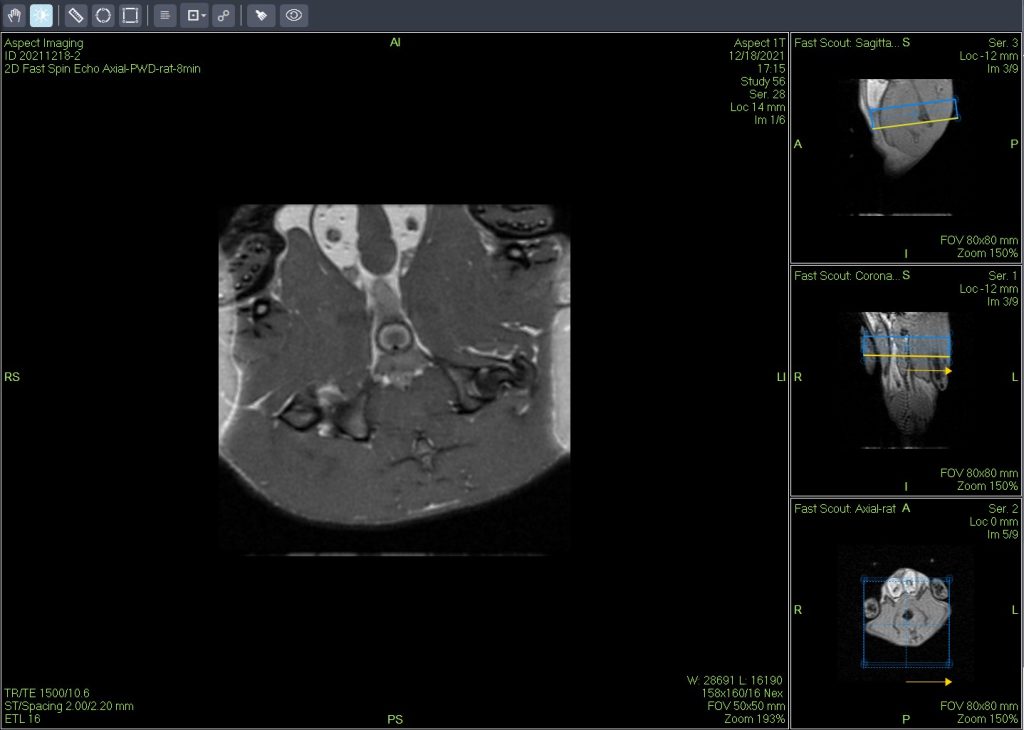

活體磁共振成像在模型小鼠中檢測(cè)到局灶性肝損傷(圖A)。肝臟的高分辨率離體MRH評(píng)估可以在小鼠(圖B和C)中鑒定幾個(gè)單獨(dú)的局灶性脂肪病變。通過(guò)常規(guī)組織病理學(xué)證實(shí)病變?yōu)榫衷钚灾靖淖儯▓DC)。